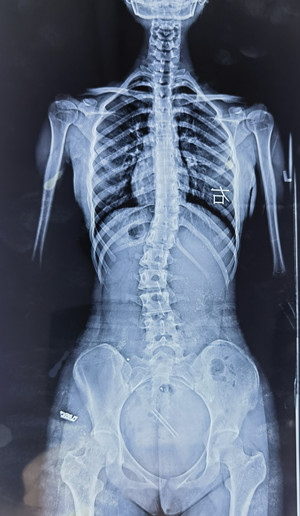

脊柱側(cè)彎的X線檢查

通過全脊柱正、側(cè)位X線檢查,能明確側(cè)彎的部位、角度、性質(zhì)、椎體旋轉(zhuǎn)程度等。要避免僅拍攝脊柱單部位X線片,因為其難以充分顯示脊柱全貌,對診斷脊柱側(cè)彎來說是局限的。

在X線檢查中,我們可以測定患者的cobb角,該角度測量是通過測量脊柱上下彎曲最頂端的兩個椎體上、下緣所成的角度,來確定側(cè)彎的嚴重程度。